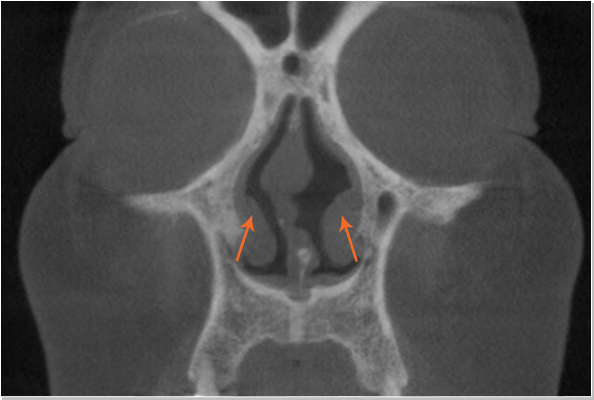

비중격만곡증 비정상

휘어있는 비중격